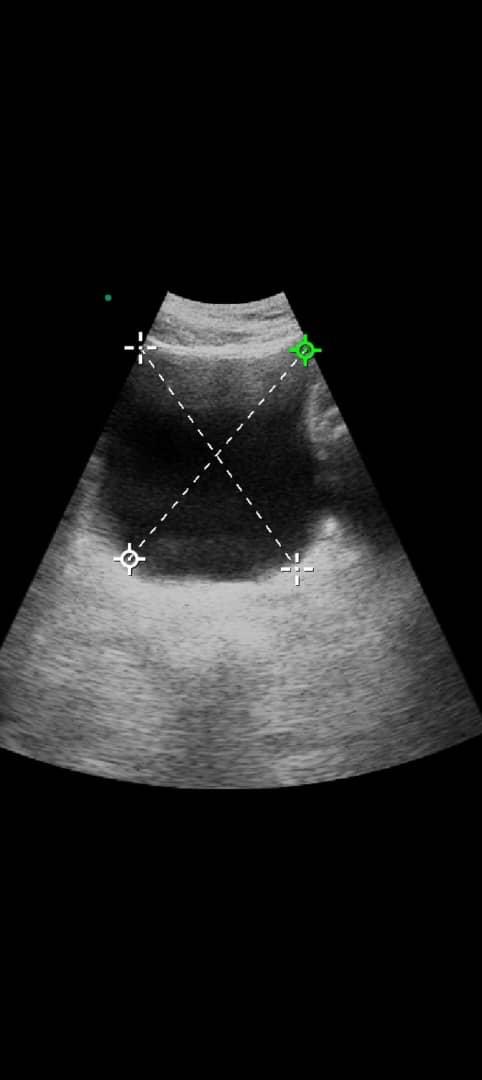

El día 3 de junio de 2025, acudió al médico con malestar general severo y sin poder orinar. Al llegar al urólogo, le realizaron una extracción inmediata de 5 litros de orina acumulada, lo que ya comprometía gravemente su salud. Luego de un ecosonograma, se le diagnosticó hiperplasia prostática benigna de grado II, la cual ya está causando insuficiencia renal.

On June 3rd, 2025, he visited the doctor with severe discomfort and an inability to urinate. At the urologist’s office, he had an emergency extraction of 5 liters of retained urine. An ultrasound revealed that he has benign prostatic hyperplasia (BPH), grade II, which is already causing kidney failure.